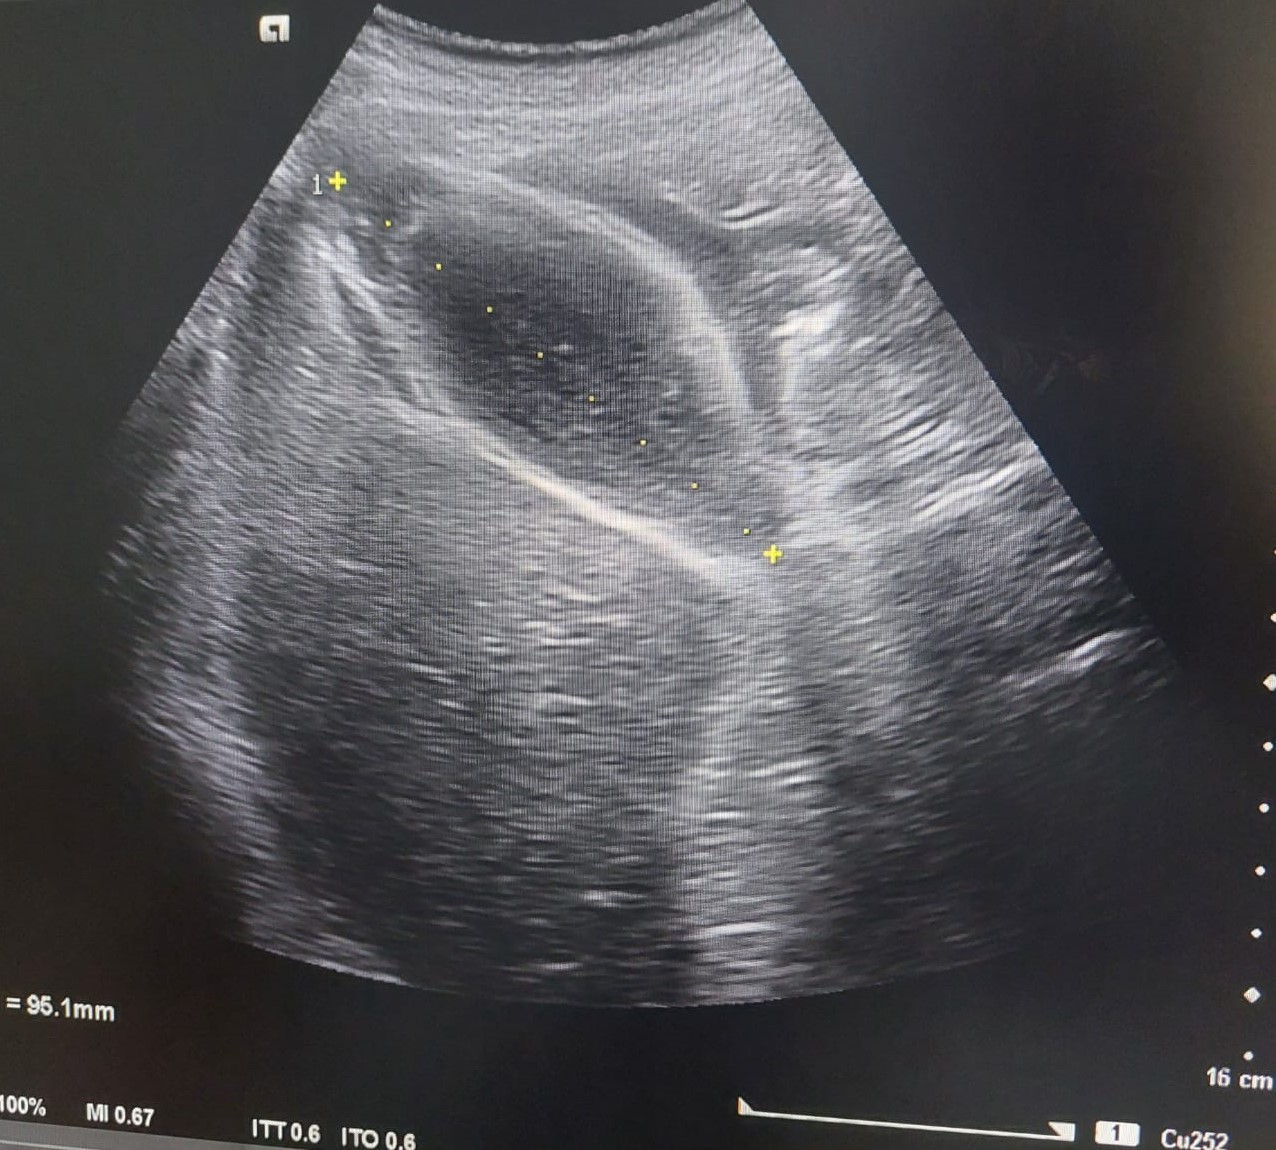

Se realiza una ecografía clínica abdominal en la que destaca un engrosamiento de la pared anterior de la vesícula biliar, sin imágenes hiperecogénicas en su interior. Parénquima hepático y riñón derecho con morfología y ecoestructura normal.

Se deriva a cirugía que solicita ecografía reglada informándola como vesícula biliar distendida, con engrosamiento marcado y limitado a la pared del fundus vesicular asociado a barro biliar. Hallazgos no concluyentes para colecistitis aguda, y podría estar en relación con adenomiomatosis del fundus asociado a barro biliar, o menos probable colecistitis subaguda.